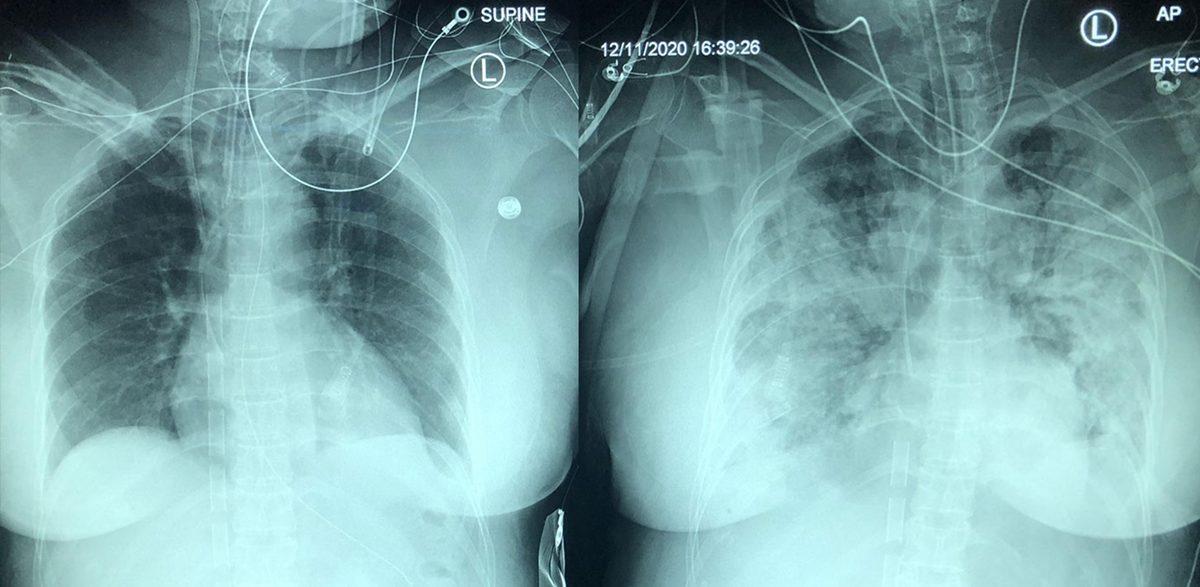

- Covid'de zatürrenin 5 gün içindeki yayılışı